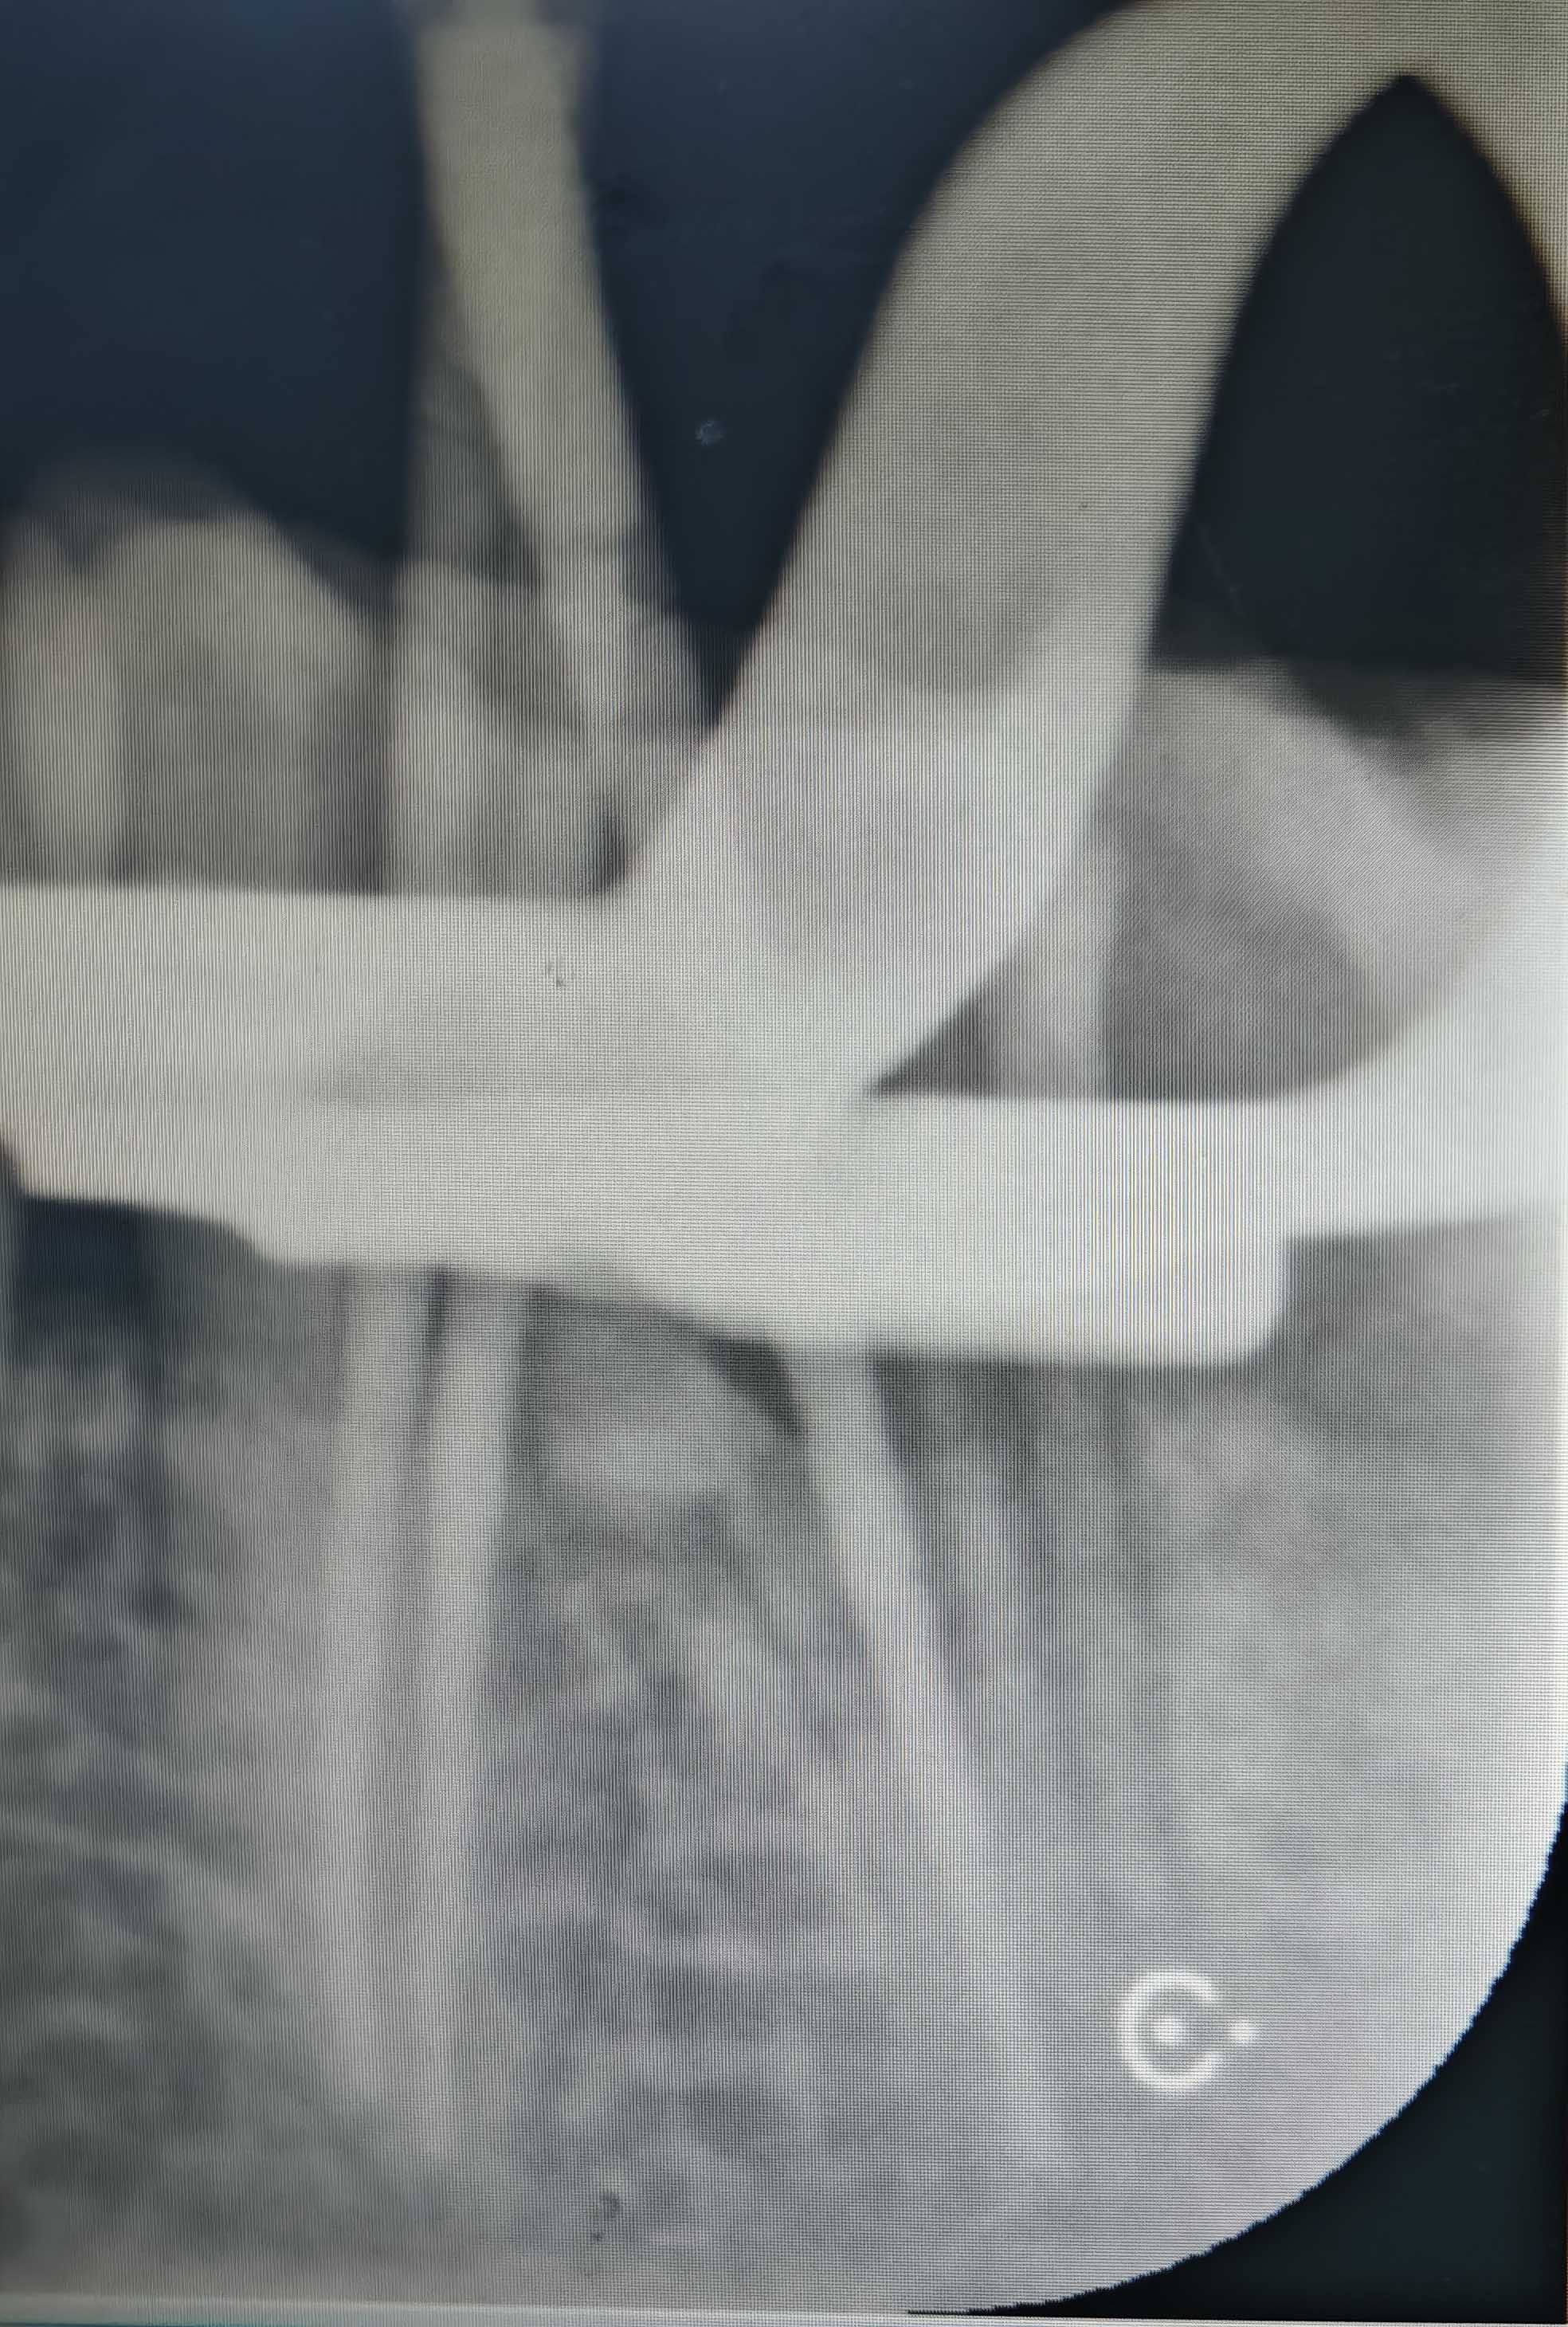

根管治疗 - 案例二

术前 术前

术后 术后